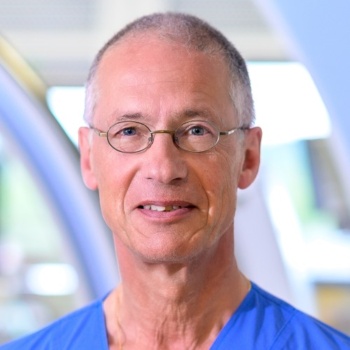

Prof. Iris Grunwald

Diagnostic and Interventional Neuroradiologist and Clinical Professor for Imaging and Science and Technology at University of Dundee, Scotland

Prof. Bob Geelkerken

Consultant vascular surgeon, University of Twente, former chair of Dutch Society of Vascular Surgery